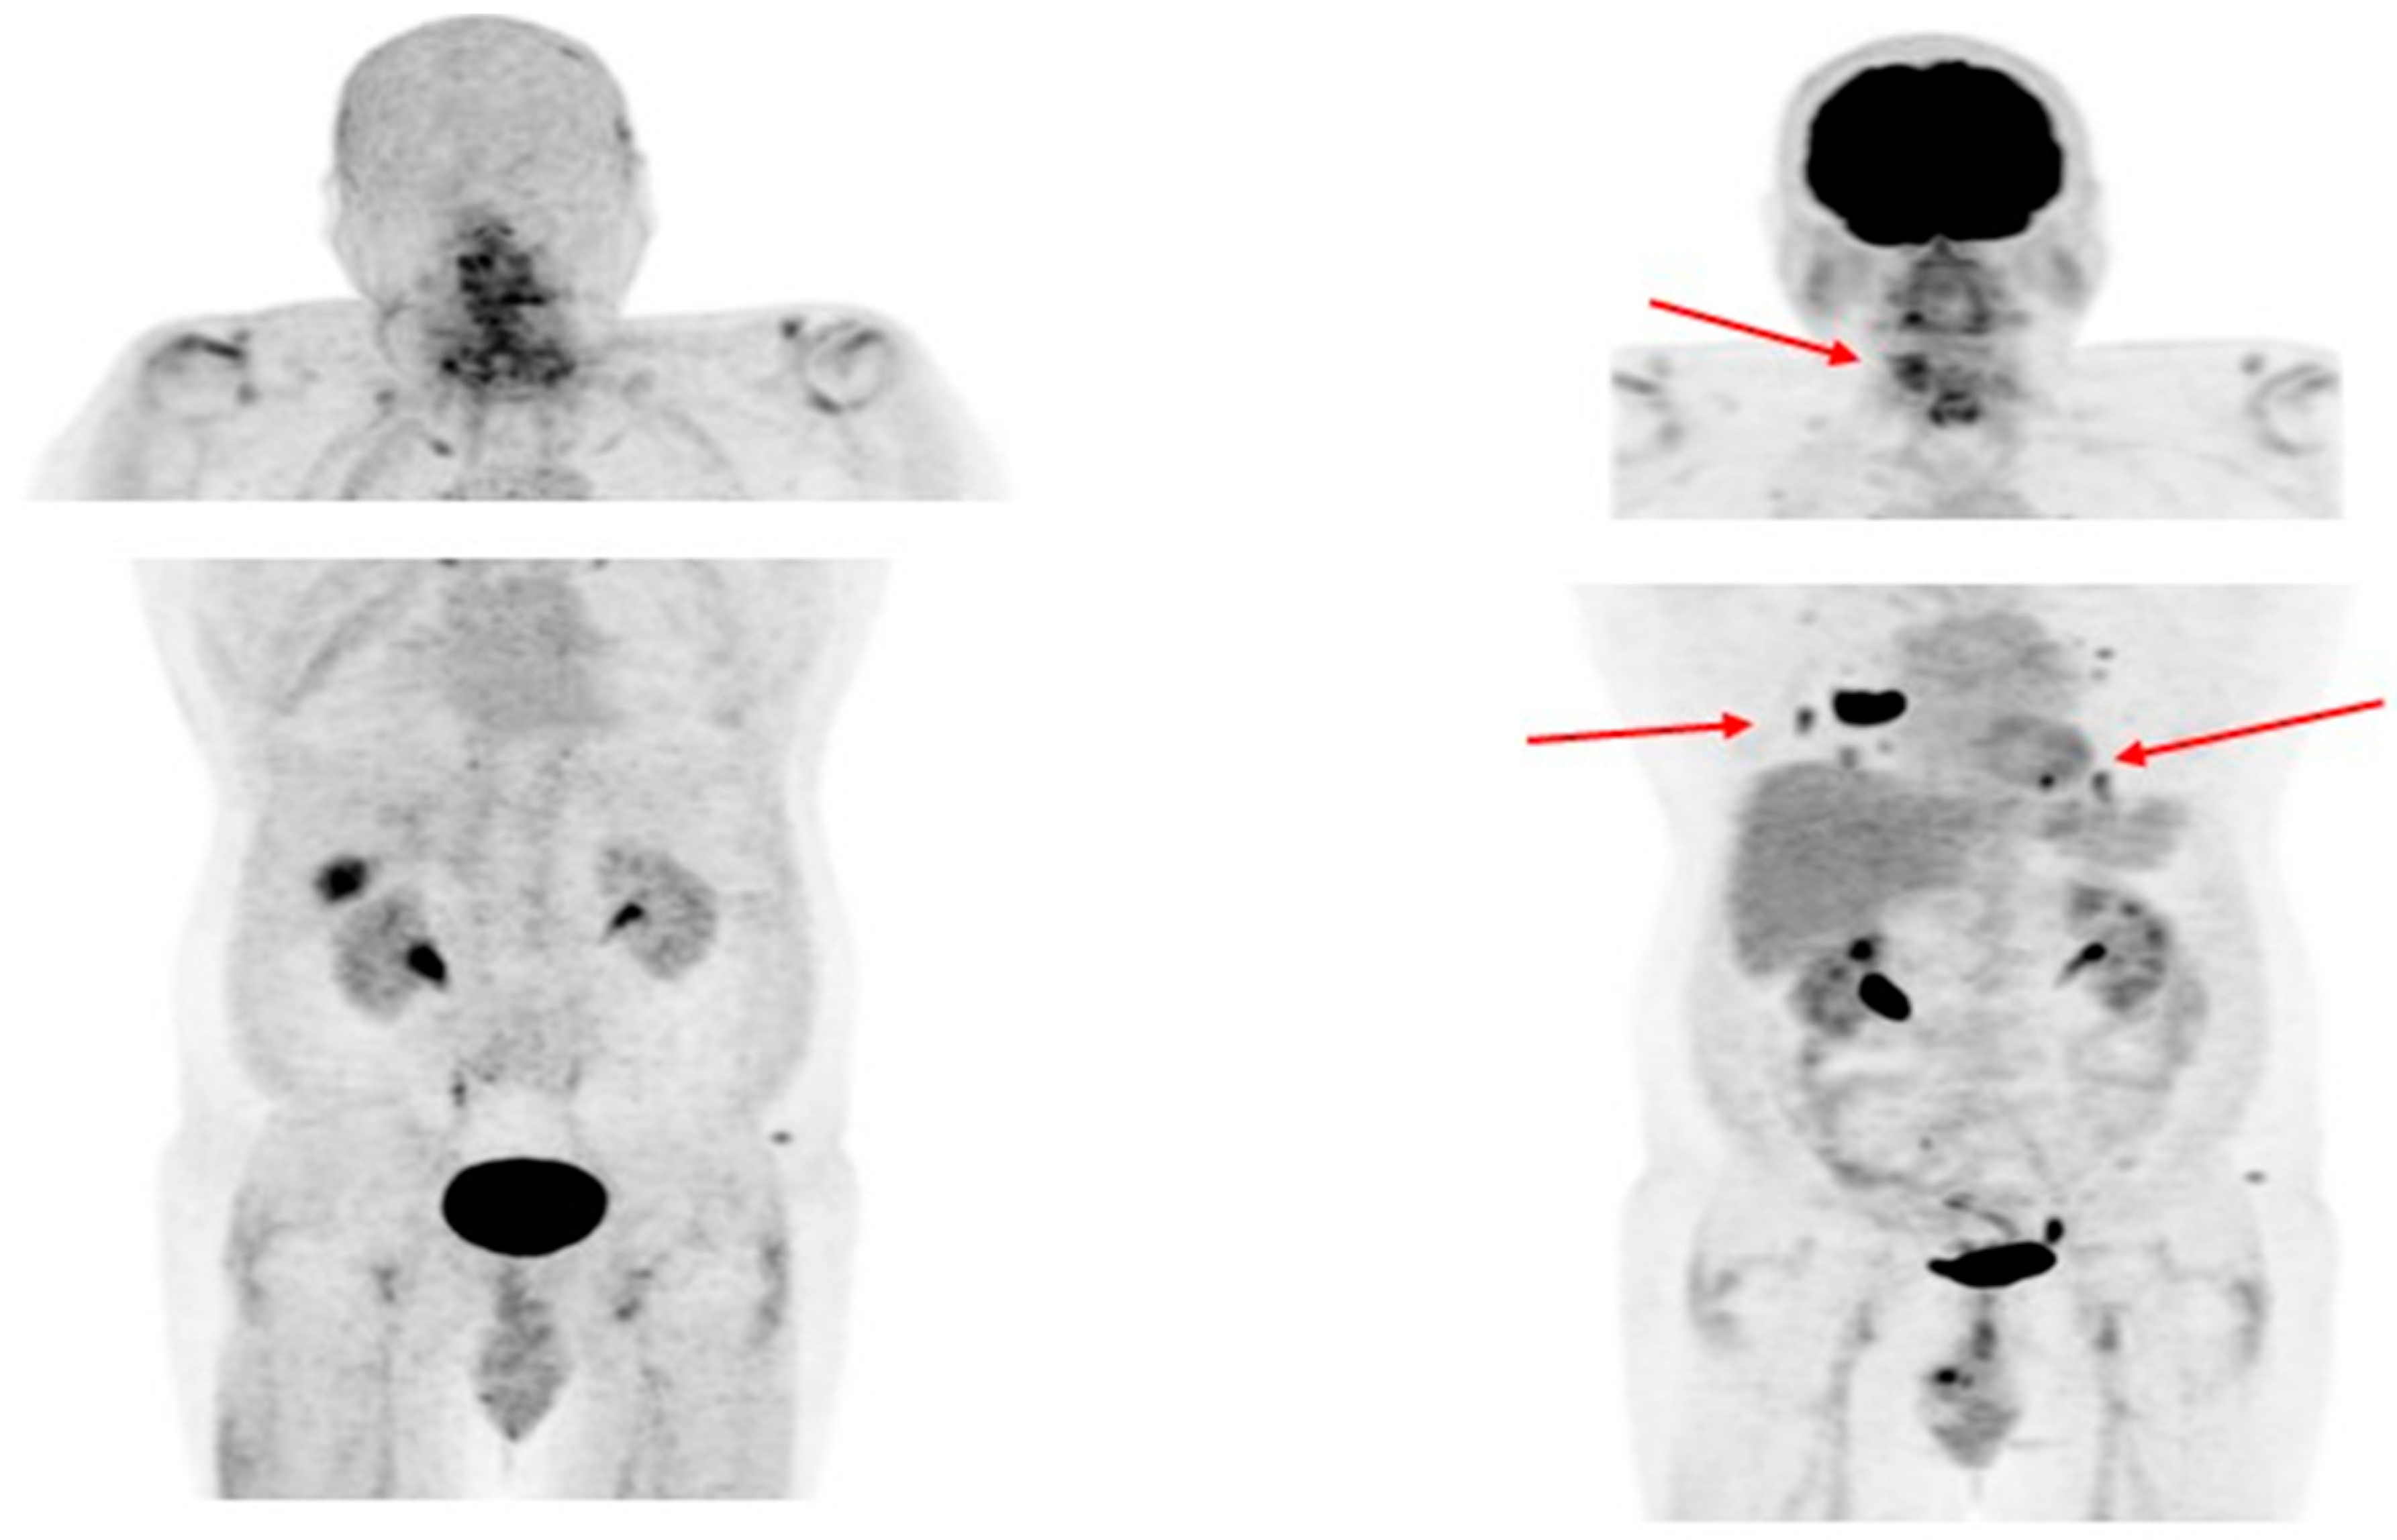

- Chen, Y.; Zheng, S.; Zhang, J.; Yao, S.; Miao, W. 68Ga-DOTA-FAPI-04 PET/CT Imaging in Radioiodine-Refractory Differentiated Thyroid Cancer (RR-DTC) Patients. Ann. Nucl. Med. 2022, 36, 610–622. [Google Scholar] [CrossRef] [PubMed]

- Fu, H.; Fu, J.; Huang, J.; Pang, Y.; Chen, H. 68Ga-FAPI PET/CT Versus 18F-FDG PET/CT for Detecting Metastatic Lesions in a Case of Radioiodine-Refractory Differentiated Thyroid Cancer. Clin. Nucl. Med. 2021, 46, 940–942. [Google Scholar] [CrossRef] [PubMed]

- Ballal, S.; Yadav, M.P.; Moon, E.S.; Roesch, F.; Kumari, S.; Agarwal, S.; Tripathi, M.; Sahoo, R.K.; Mangu, B.S.; Tupalli, A.; et al. Novel Fibroblast Activation Protein Inhibitor-Based Targeted Theranostics for Radioiodine-Refractory Differentiated Thyroid Cancer Patients: A Pilot Study. Thyroid 2022, 32, 65–77. [Google Scholar] [CrossRef]